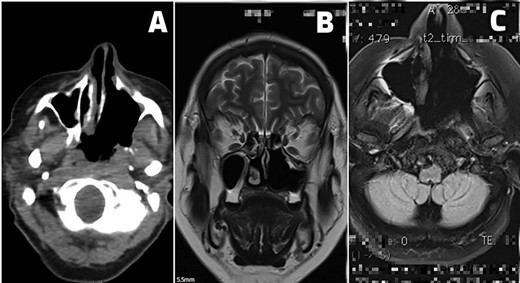

A 61-year-old female patient presented with history of disease lasted for 5 years before hospital admission. Symptoms included nasal obstruction with consecutive conductive hearing loss, hyposmia, nasal discharge and nasality in speech. Nasal endoscopic examination showed a tumor mass in the posterior part of the left nasal cavity occupying both sides of the nasopharyngeal space. Multi-slice CT scan and MRI revealed a destructive tumor mass 4 × 5 cm primary located in the region of paranasal sinuses on the left side with suspected tumor spread in the nasopharynx, upper parapharyngeal space and petroclival region with rather extensive skull base involvement, as it is demonstrated in Fig. 1.

(A and B) Preoperative scan (A-axial CT scan, B-sagittal MRI scan). Multi-sliced CT and MRI scan revealed a destructive mass 4 × 5 cm in the posterior third of the left nasal cavity, left ethmoid and left maxillary sinus spreading into nasopharynx predominantly on patients left side, but occluding both choanae (tumor in white oval). Tumor spread included left great wing of the sphenoid bone, along the left petroclival fissure and the apex of the left temporal bone.